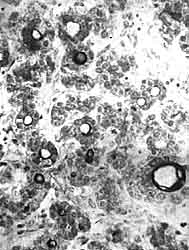

Коллоид, дающий PAS-положительную реакцию (черный), в фолликулах щитовидной железы. Плод длиной 49 мм.

Вначале зачаток щитовидной железы состоит из эпителиальных тяжей, которые ветвятся и анастомозируют между собой. В течение 3-го месяца по ходу эпителиальных тяжей образуются перетяжки, придающие им четкообразный вид. Одновременно с этим в центре каждого сегмента, ограниченного двумя соседними перетяжками, появляются просветы. Перетяжки затем углубляются, и эпителиальные тяжи распадаются на отдельные пузырьки, или фолликулы. Образование фолликулов обычно начинается на периферии зачатка щитовидной железы, в то время как в центральных его частях еще долгое время сохраняются тяжи и плоные массы эпиетелиальных клеток.